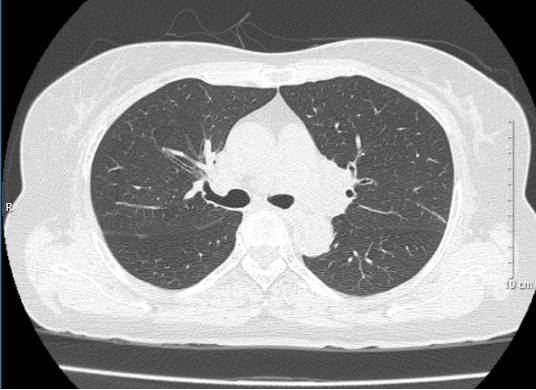

• Hình ảnh chụp cắt lớp vi tính lồng ngực sau 3 chu kì điều trị: Không thấy tổn thương khu trú hoặc lan tỏa nhu mô hai phổi. Không có hạch trung thất.

Hình 2: Hình ảnh trước điều trị (bên trái): Hình ảnh khối u và tổn thương di căn phổi cùng bên (mũi tên đỏ). Hình ảnh sau điều trị (bên phải): không còn khối u sau 3 chu kì điều trị

Hình 3: Hình bên trái (trước điều trị): Hình ảnh khối u (mũi tên vàng). Hình bên phải (sau điều trị): không còn tổn thương di căn phổi cùng bên sau 3 chu kì điều trị